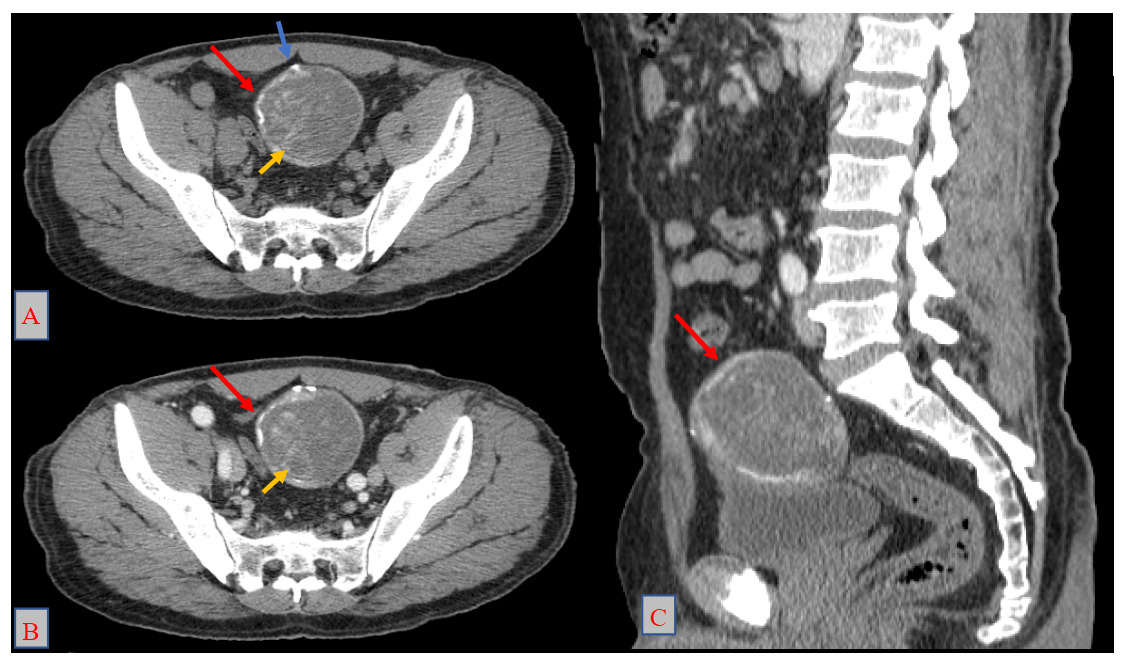

Physical examination was unremarkable. Abdominopelvic ultrasound revealed a supravesical cystic lesion with a thickened wall, classified as Gharbi type III, measuring 53 × 61 mm (Figure 1). Contrast-enhanced CT confirmed a well-defined supravesical cyst, approximately 80 × 60 mm, displacing the bladder inferiorly, with no evidence of adjacent tissue invasion or other hydatid localizations (Figure 2). Serological testing for hydatid disease was positive, further supporting the diagnosis.